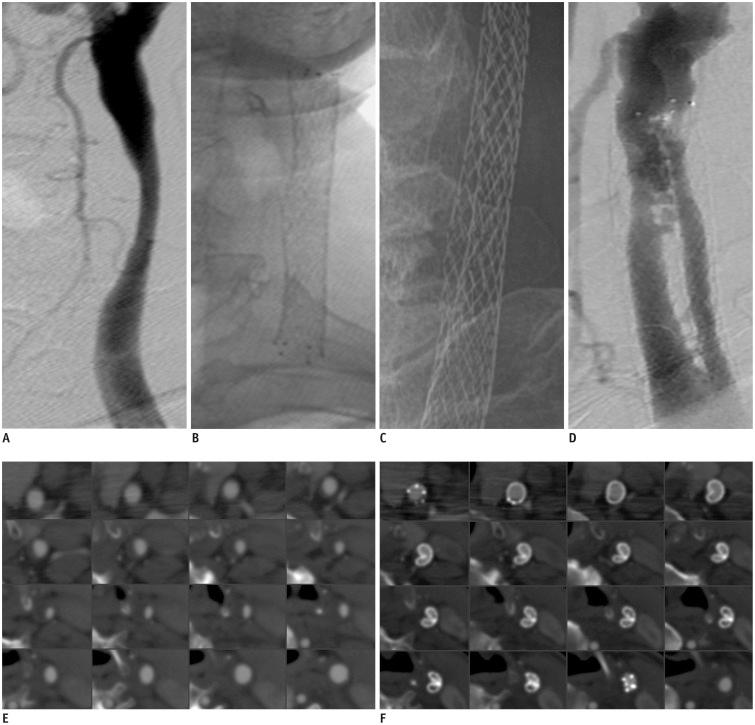

We report a case of delayed cerebral infarction due to stent longitudinal folding deformation following carotid artery stenting using a self-expandable stent with an open-cell design. The stented segment of the left common carotid artery was divided into two different lumens by this folding deformation, and the separated lumens became restricted with in-stent thrombosis. Although no established method of managing this rare complication exists, a conservative approach was taken with administration of anticoagulant and dual antiplatelet therapy. No neurological symptoms were observed during several months of clinical follow-up after discharge.

我们报告了一例使用具有开孔设计的自膨式支架行颈动脉支架置入术后因支架纵向折叠变形导致的迟发性脑梗死。这种折叠变形将左颈总动脉支架段分隔成两个不同的管腔,分隔的管腔因支架内血栓形成而受限。尽管对于这种罕见的并发症尚无既定的处理方法,但我们采取了保守的方法,给予抗凝和双联抗血小板治疗。出院后数月的临床随访中,未观察到神经症状。